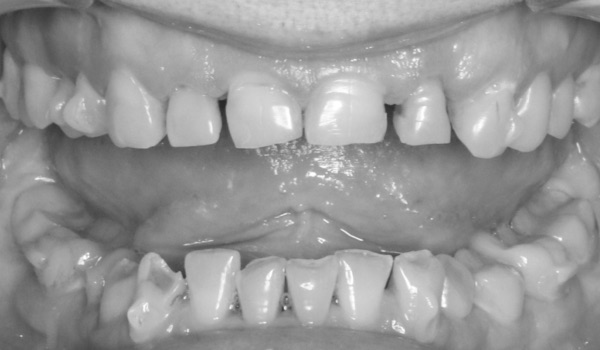

Истории лечения наших пациентов в формате "до-после"

1. Диагностика и проф. гигиена

оцениваем состояние зубов и проводим полную санацию